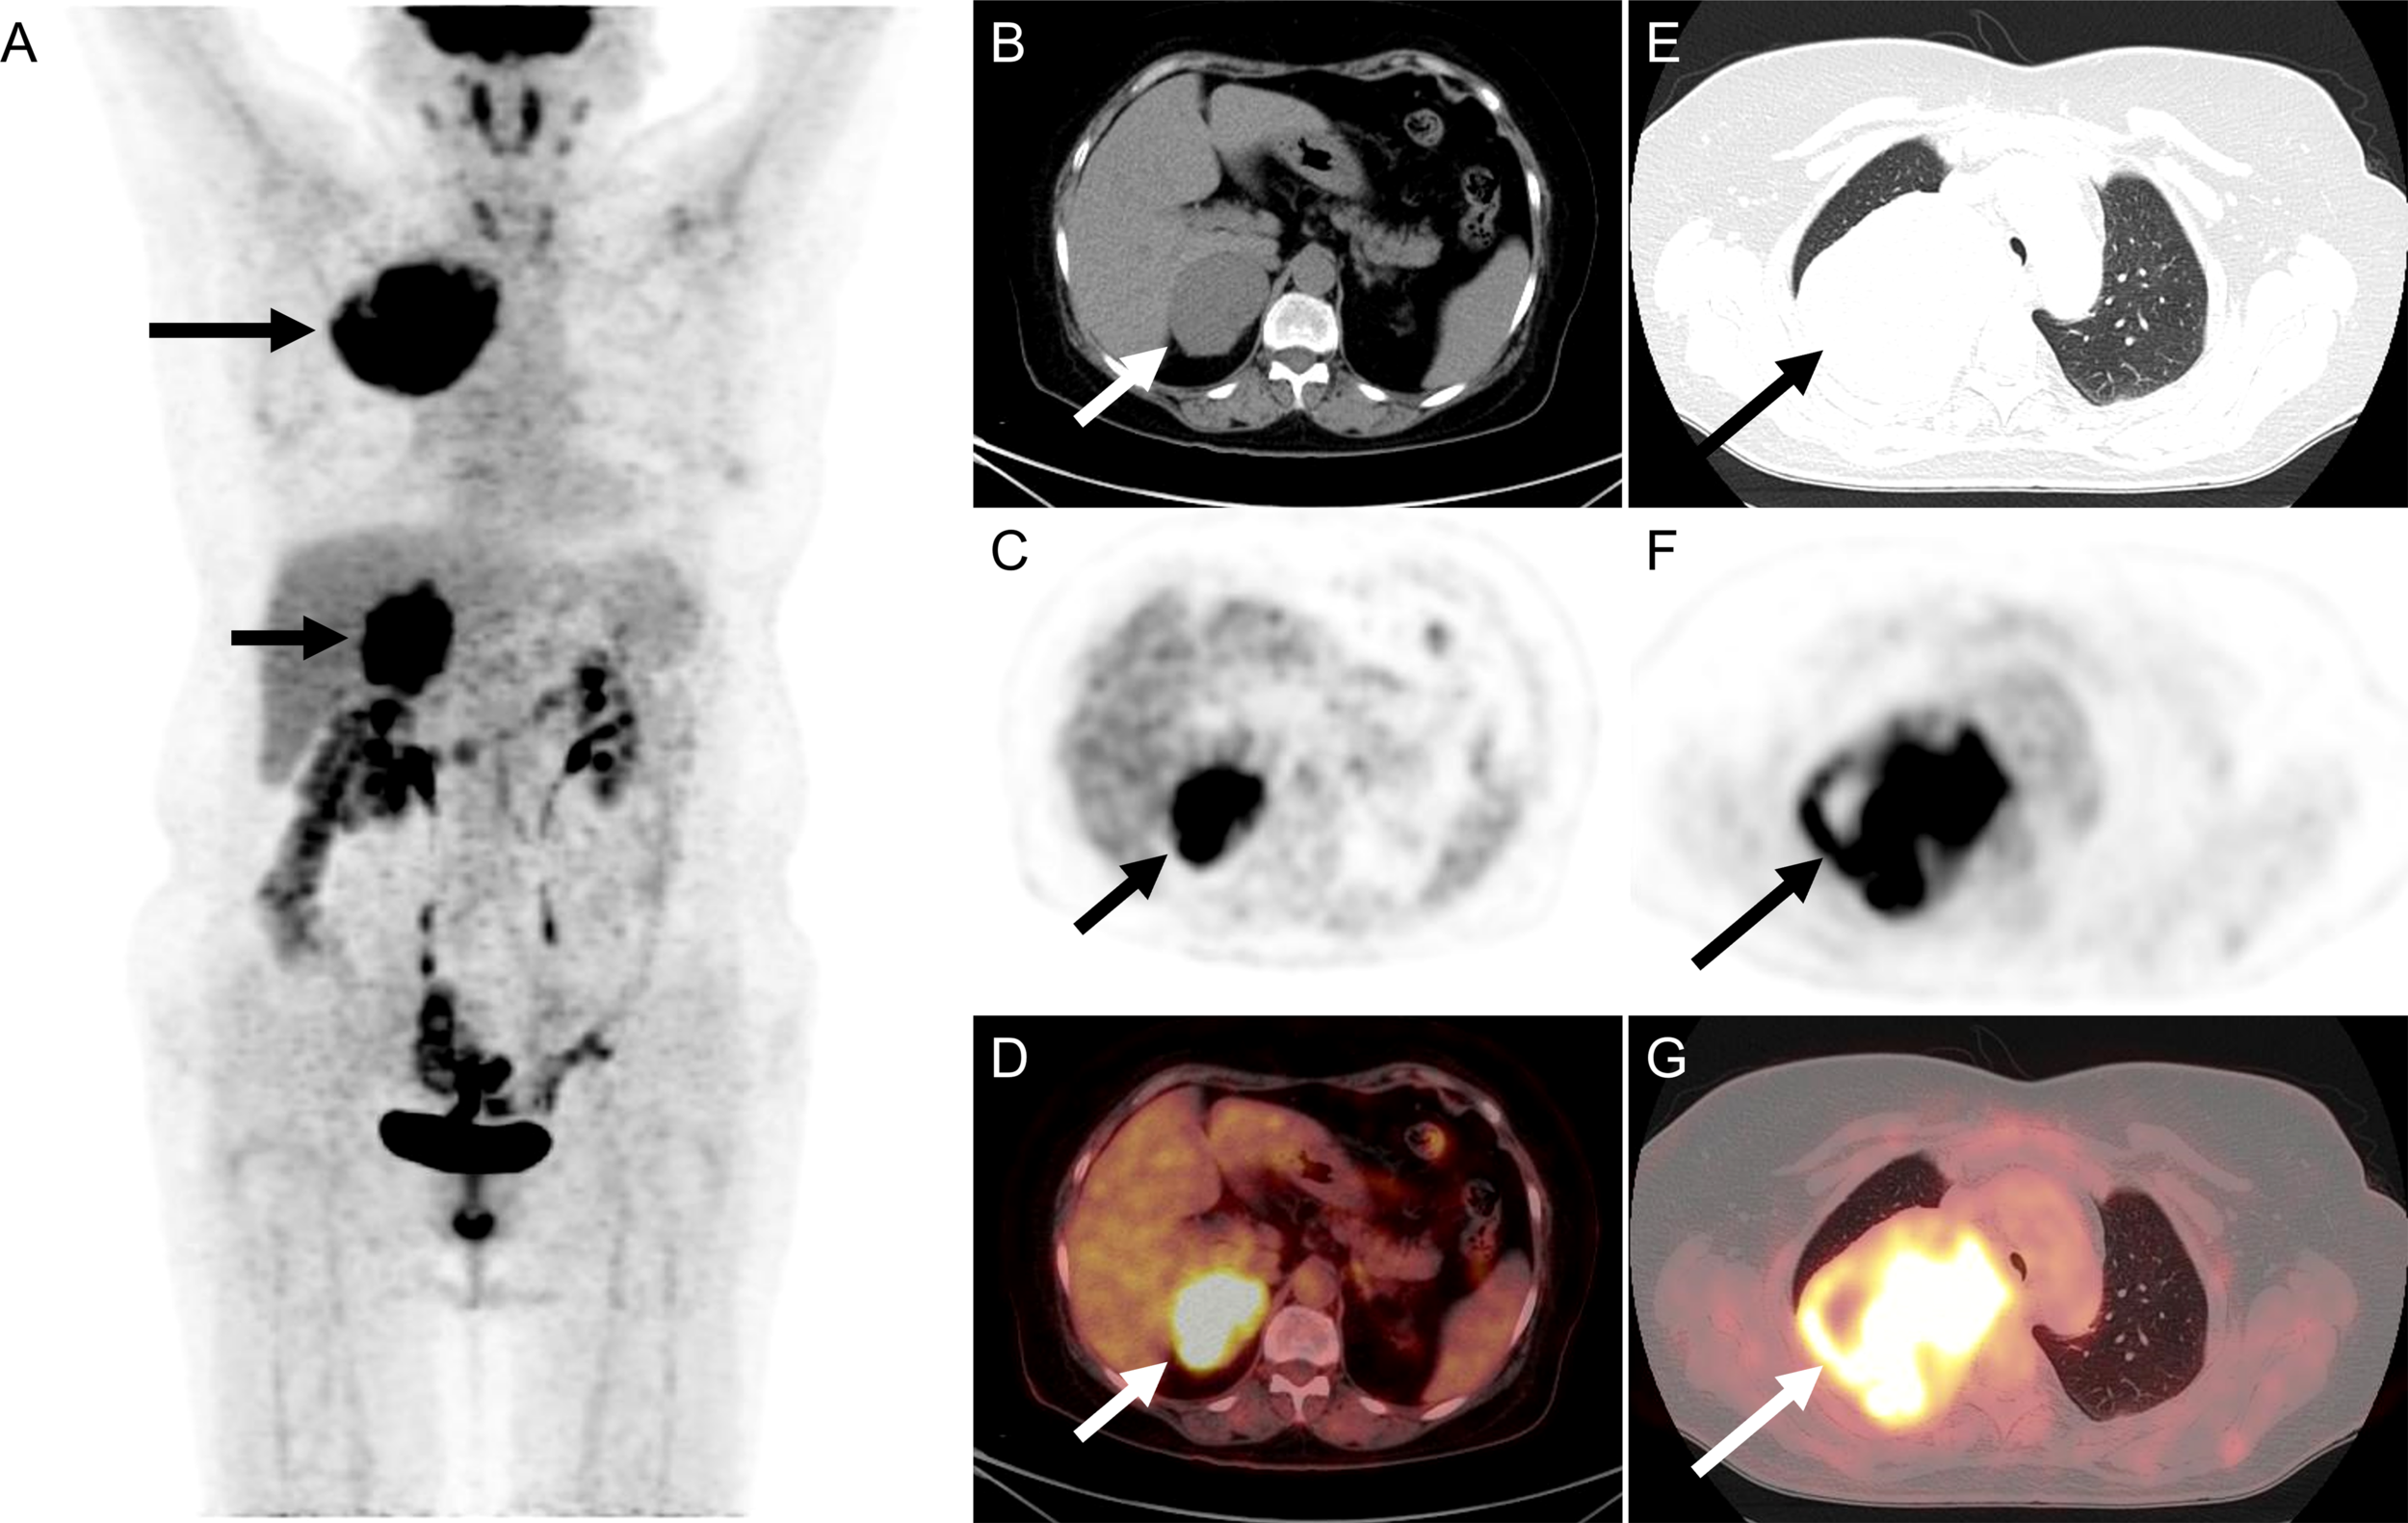

18F-FDG PET/CT was performed to identify if there was a potential malignancy tumor. The maximum intensity projection image (Figure 1A) revealed hypermetabolic lesions in the right thorax ((long arrow) and the right upper abdomen (short arrow). On the axial CT (Figure 1B), PET (Figure 1C), and fused PET/CT (Figure 1D) showed a large irregular lesion in the right lung upper lobe, measuring 8.4 cm×10.2 cm×8.1 cm showing intense 18F-FDG uptake with SUVmax of 13.4. The axial CT (Figure 1E), PET (Figure 1F), and fused PET/CT (Figure 1G) revealed the increased activity corresponded to a slight hypodense right adrenal gland soft tissue mass, measuring 5.1 cm×6.3 cm×6.5 cm showing intense 18F-FDG uptake with SUVmax of 13.4. The patient underwent thoracoscopic resection of the right upper lobe at an outside hospital, and postoperative pathology diagnosed high-grade ESS metastasis to the right side of the lung. The patient had follow-up outside the hospital. After 2 months, the ultrasound revealed a right adrenal mass that was 9.1 × 6.5 cm. After 5 months, the 18F-FDG PET/CT revealed a right adrenal mass that was 11.4 cm × 11.0 cm × 10.8 cm. After a period of recuperation at home, she was came to our hospital for further treatment.

Figure 1

The 18F-FDG PET/CT of patient before operation. (A) The image revealed hypermetabolic lesions in the right thorax (long arrow) and the right upper abdomen (short arrow). (B–D) On the axial CT, PET, and fused PET/CT showed a large irregular lesion in the right lung upper lobe, measuring 8.4 cm×10.2 cm×8.1 cm showing intense 18F-FDG uptake with SUVmax of 13.4. (E–G) The axial CT, PET, and fused PET/CT revealed the increased activity corresponded to a slight hypodense right adrenal gland soft tissue mass, measuring 5.1 cm×6.3 cm×6.5 cm showing intense 18F-FDG uptake with SUVmax of 13.4.